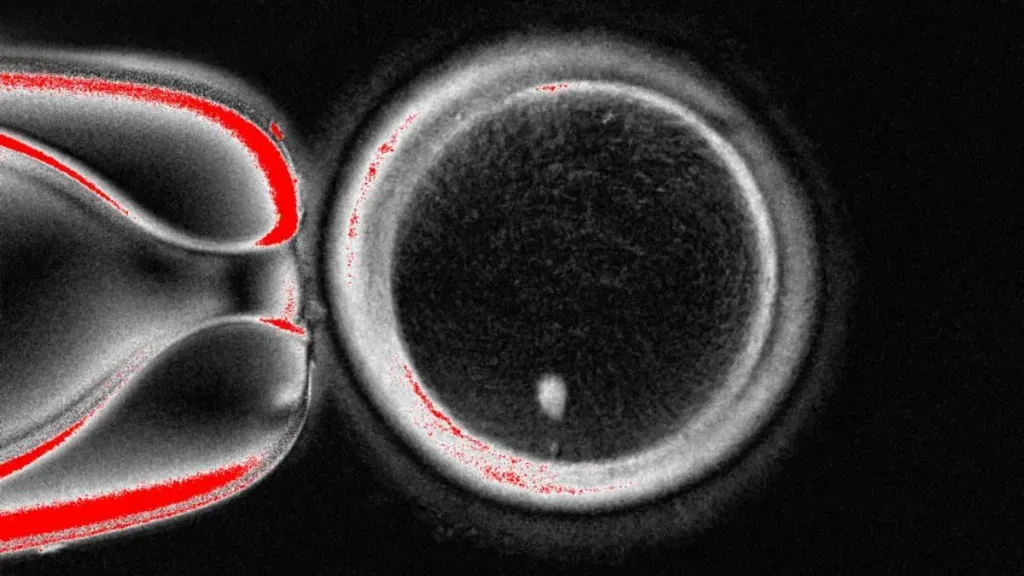

ისტორიაში პირველად, ამერიკელმა მეცნიერებმა ადამიანის კანის უჯრედებიდან აღებული დნმ-გან ემბრიონის შექმნა შეძლეს. კერძოდ, მოპოვებული დნმ-ი იმავე კანდიდატის სპერმით გაანაყოფიერეს, რის შემდეგაც ემბრიონი წარმოიქმნა.

აქამდე რეპროდუქტოლოგიის დარგი ქალის კვერცხუჯრედის კაცის სპერმით განაყოფიერებით შემოიფარგლებოდა, რის შედეგადაც ისახება ემბრიონი, 9 თვეში კი ბავშვი ჩნდება. ახლა მეცნიერები წესებს ცვლიან. მათ ადამიანის მთლიანი გენეტიკური კოდის შემცველი უჯრედი კანიდან აიღეს და დონორის კვერცხუჯრედში მოათავსეს, რომელიც მანამდე გენეტიკური მასალისგან დაცალეს.